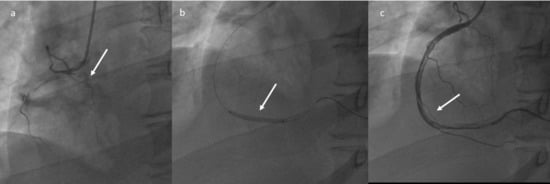

The patient was transferred to the Hemodynamics room at 1.00 p.m. a plain old balloon angioplasty (POBA) of the right coronary artery was performed, without stent implantation, with restoration of distal flow, but with persistence of extensive thrombosis of the vessel (Figure 3) with a theoretic indication for administration of intracoronary antiplatelet agents (Aggrastat). However, given the hematological and neurological status, such therapy was not performed. A progressive worsening of the neurological state was observed until a comatose status (GCS 6) started during the procedure. The patient was transferred to the Intensive Care Unit.

Figure 3.

Plain Old Balloon Angioplasty (POBA) of the right coronary artery (a–c): restoration of the distal flow, with persistence of extensive thrombosis.